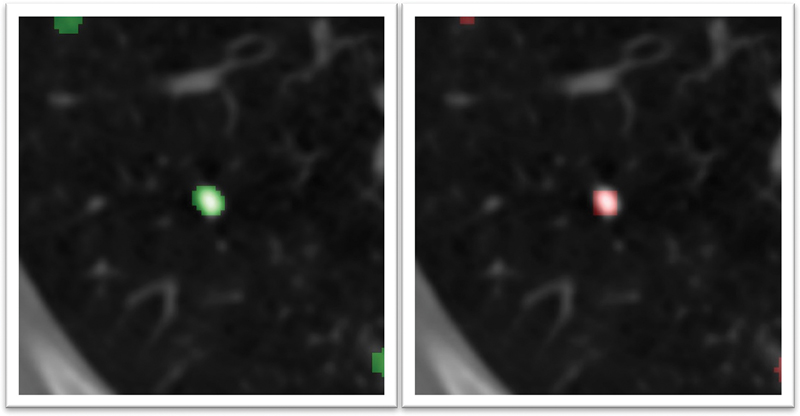

The nodule detection setting locates the nodules by predicting 3D cubes around the nodule ([Fig. 3]). This setting makes nodule AI explainable, which can assist radiologists in scan interpretations. The predictions can be used to analyze the size and location of the nodule.

| Figure 3: Pulmonary Nodule deep learning model detected a nodule in the right lower lobe (highlighted in green) which corresponds to the nodule marked by the radiologist (highlighted in red).